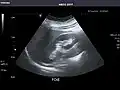

Pancreas -